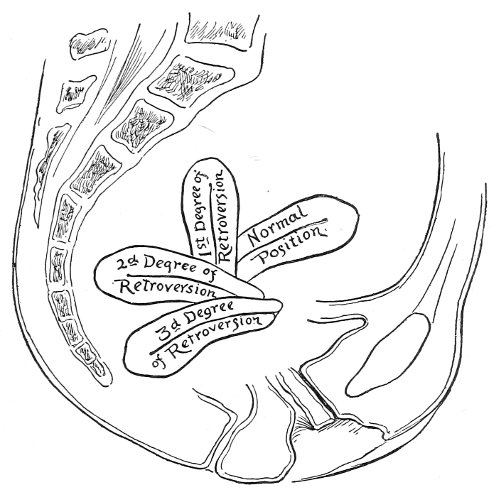

The examination of the uterus and other pelvic structures is often facilitated by dragging the uterus downward with a tenaculum while the vaginal or the bimanual examination is being made. Sensation in the cervix is so slight that little or no pain is experienced in this procedure. The anterior or posterior lip of the cervix is caught with the single or the double tenaculum (Fig. 4), guided along the vaginal finger or introduced through the speculum, and the uterus is drawn down by an assistant in case the bimanual examination is being made, or by the external hand of the examiner in case a simple vaginal examination is made. When this is done the utero-sacral ligaments are made tense, and can be felt like two cords extending from the sides of the cervix outward and backward to the pelvic wall. The posterior surface of the uterus can be palpated often as high up as the fundus. The method is especially useful when the examination is made by the rectum, and in this way the whole posterior surface and the fundus of the uterus may be palpated (Fig. 5).